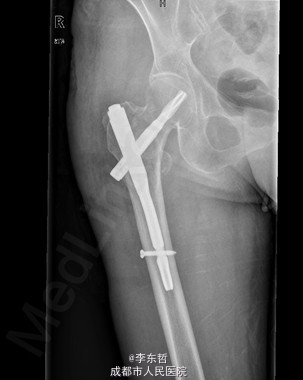

初步诊断:1、右股骨转子间骨折(Evans III型);2、骨质疏松症。 诊疗计划:1、向患者及家属交待病情及注意事项。2、向上级医生汇报患者病情。3、完善术前相关检查。4、给予皮肤牵引、抬高患肢等对症处理。5、拟手术治疗。6、密切观察病情变化,根据病情及时处理。

随访无特殊